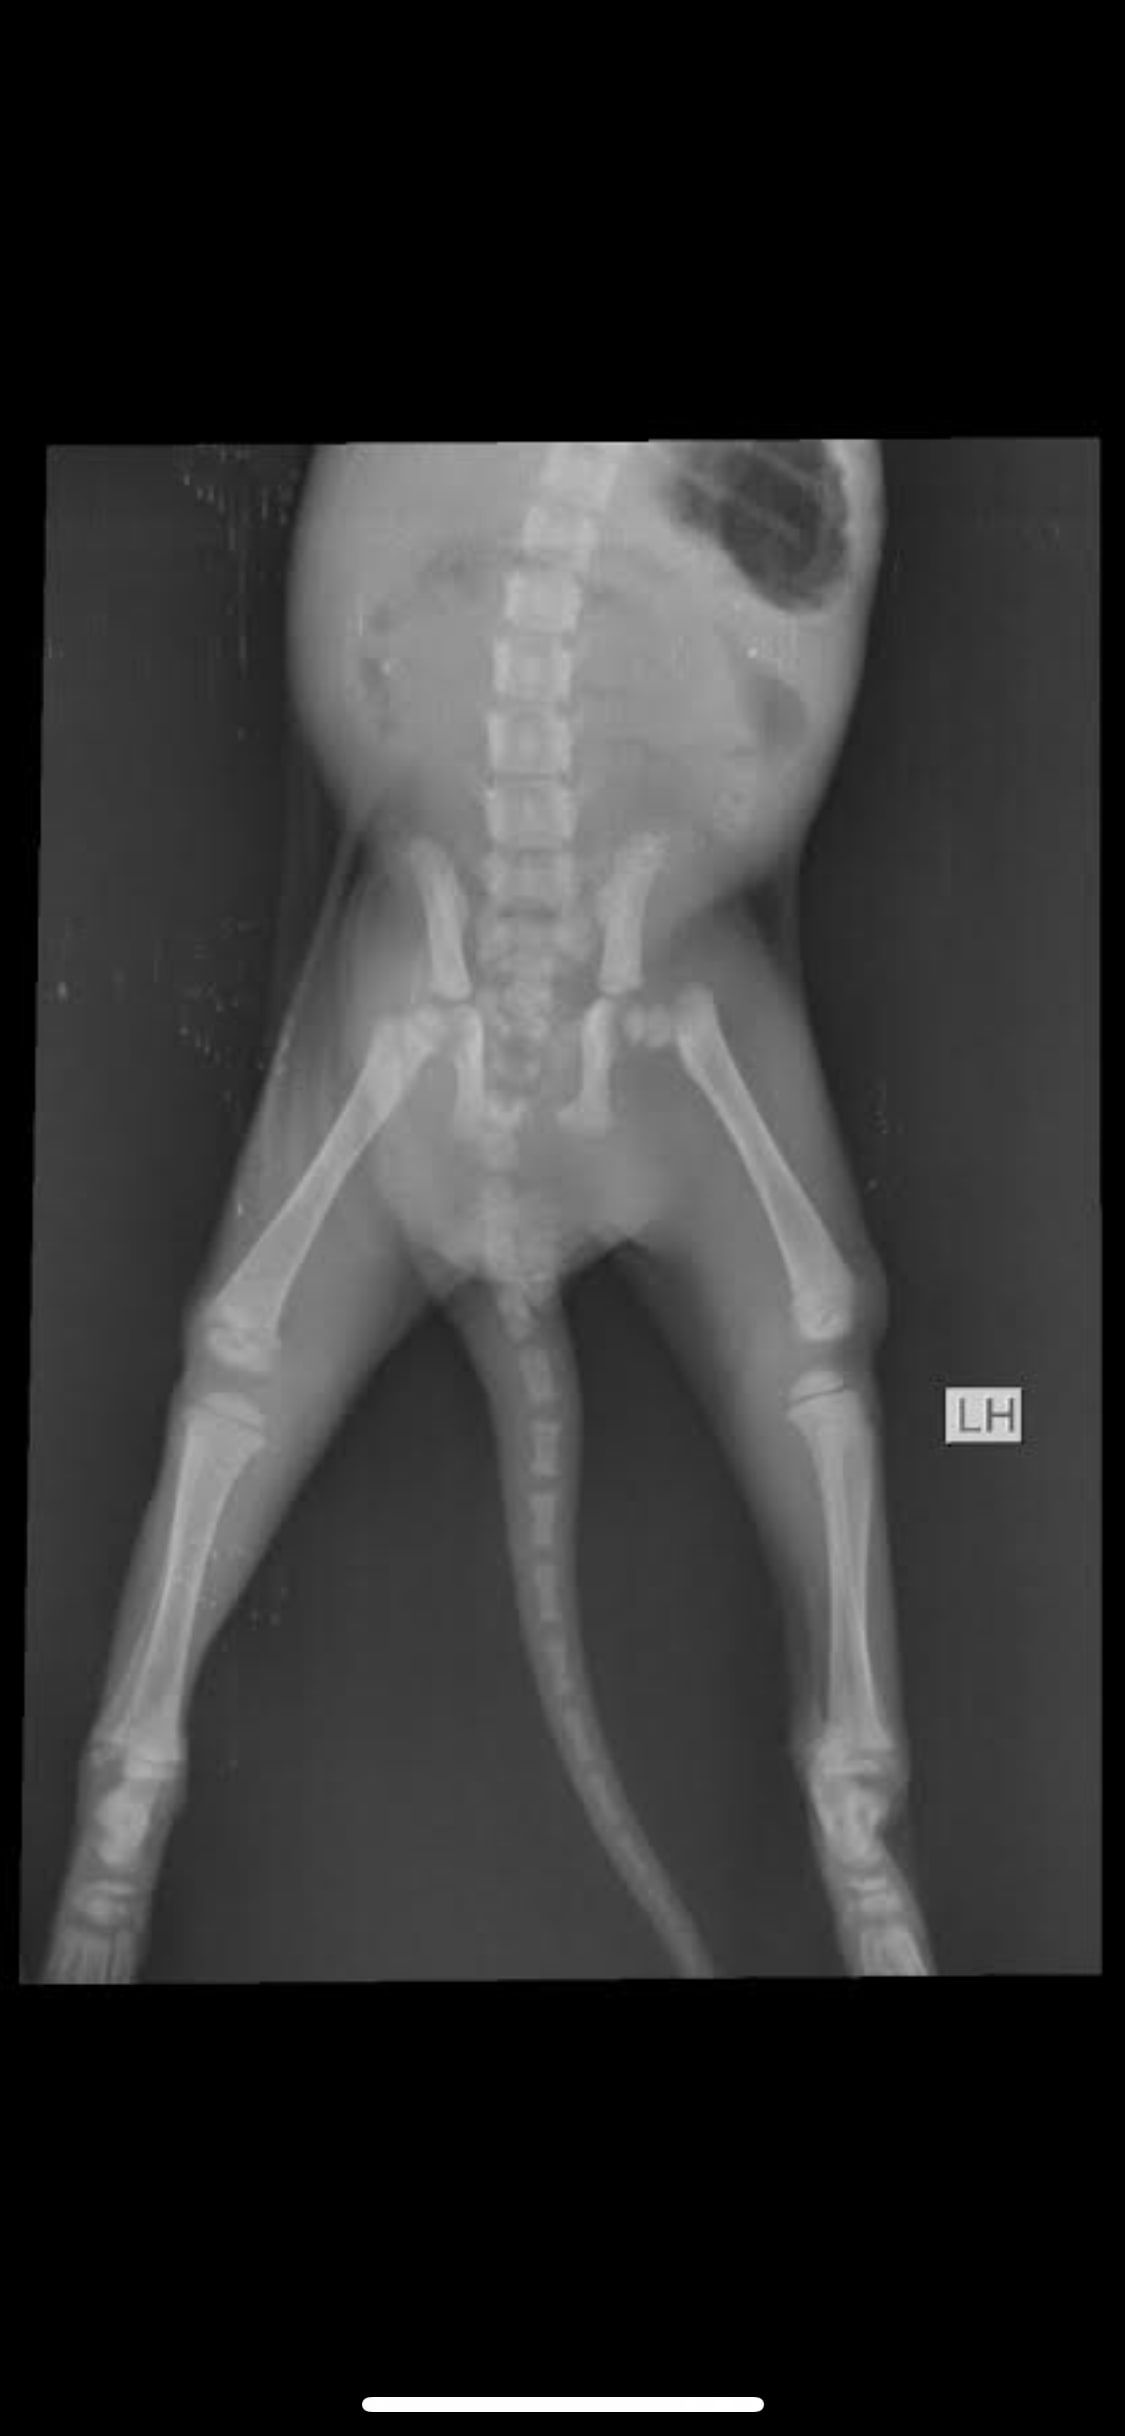

Stray cat estimated 3 months old found with presumed broken hip and leg. Took him to 3 vets but we live in a country where vets aren’t the best and they said there’s nothing we can do he’s too small to go into surgery. What do you recommend we do? Should we give him a makeshift cast? If so, how?

It's a little difficult to see in your copy of the x-ray, but it looks like the left femur might be fractured. If the broken bone is above the knee then a cast won't help because it's not possible to stabilize the fracture. If they have recommended pain medication and rest I think that probably is the best option with a broken hip - kittens can heal quickly and it's possible that he will have decent function in the leg. If not, then a surgery called a femoral head osteotomy might be an option once he's big enough for surgery.